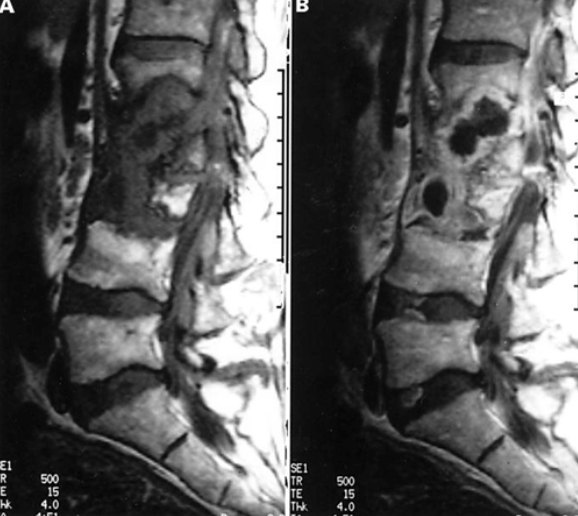

Ct myelogram

MRI w gadolinlium